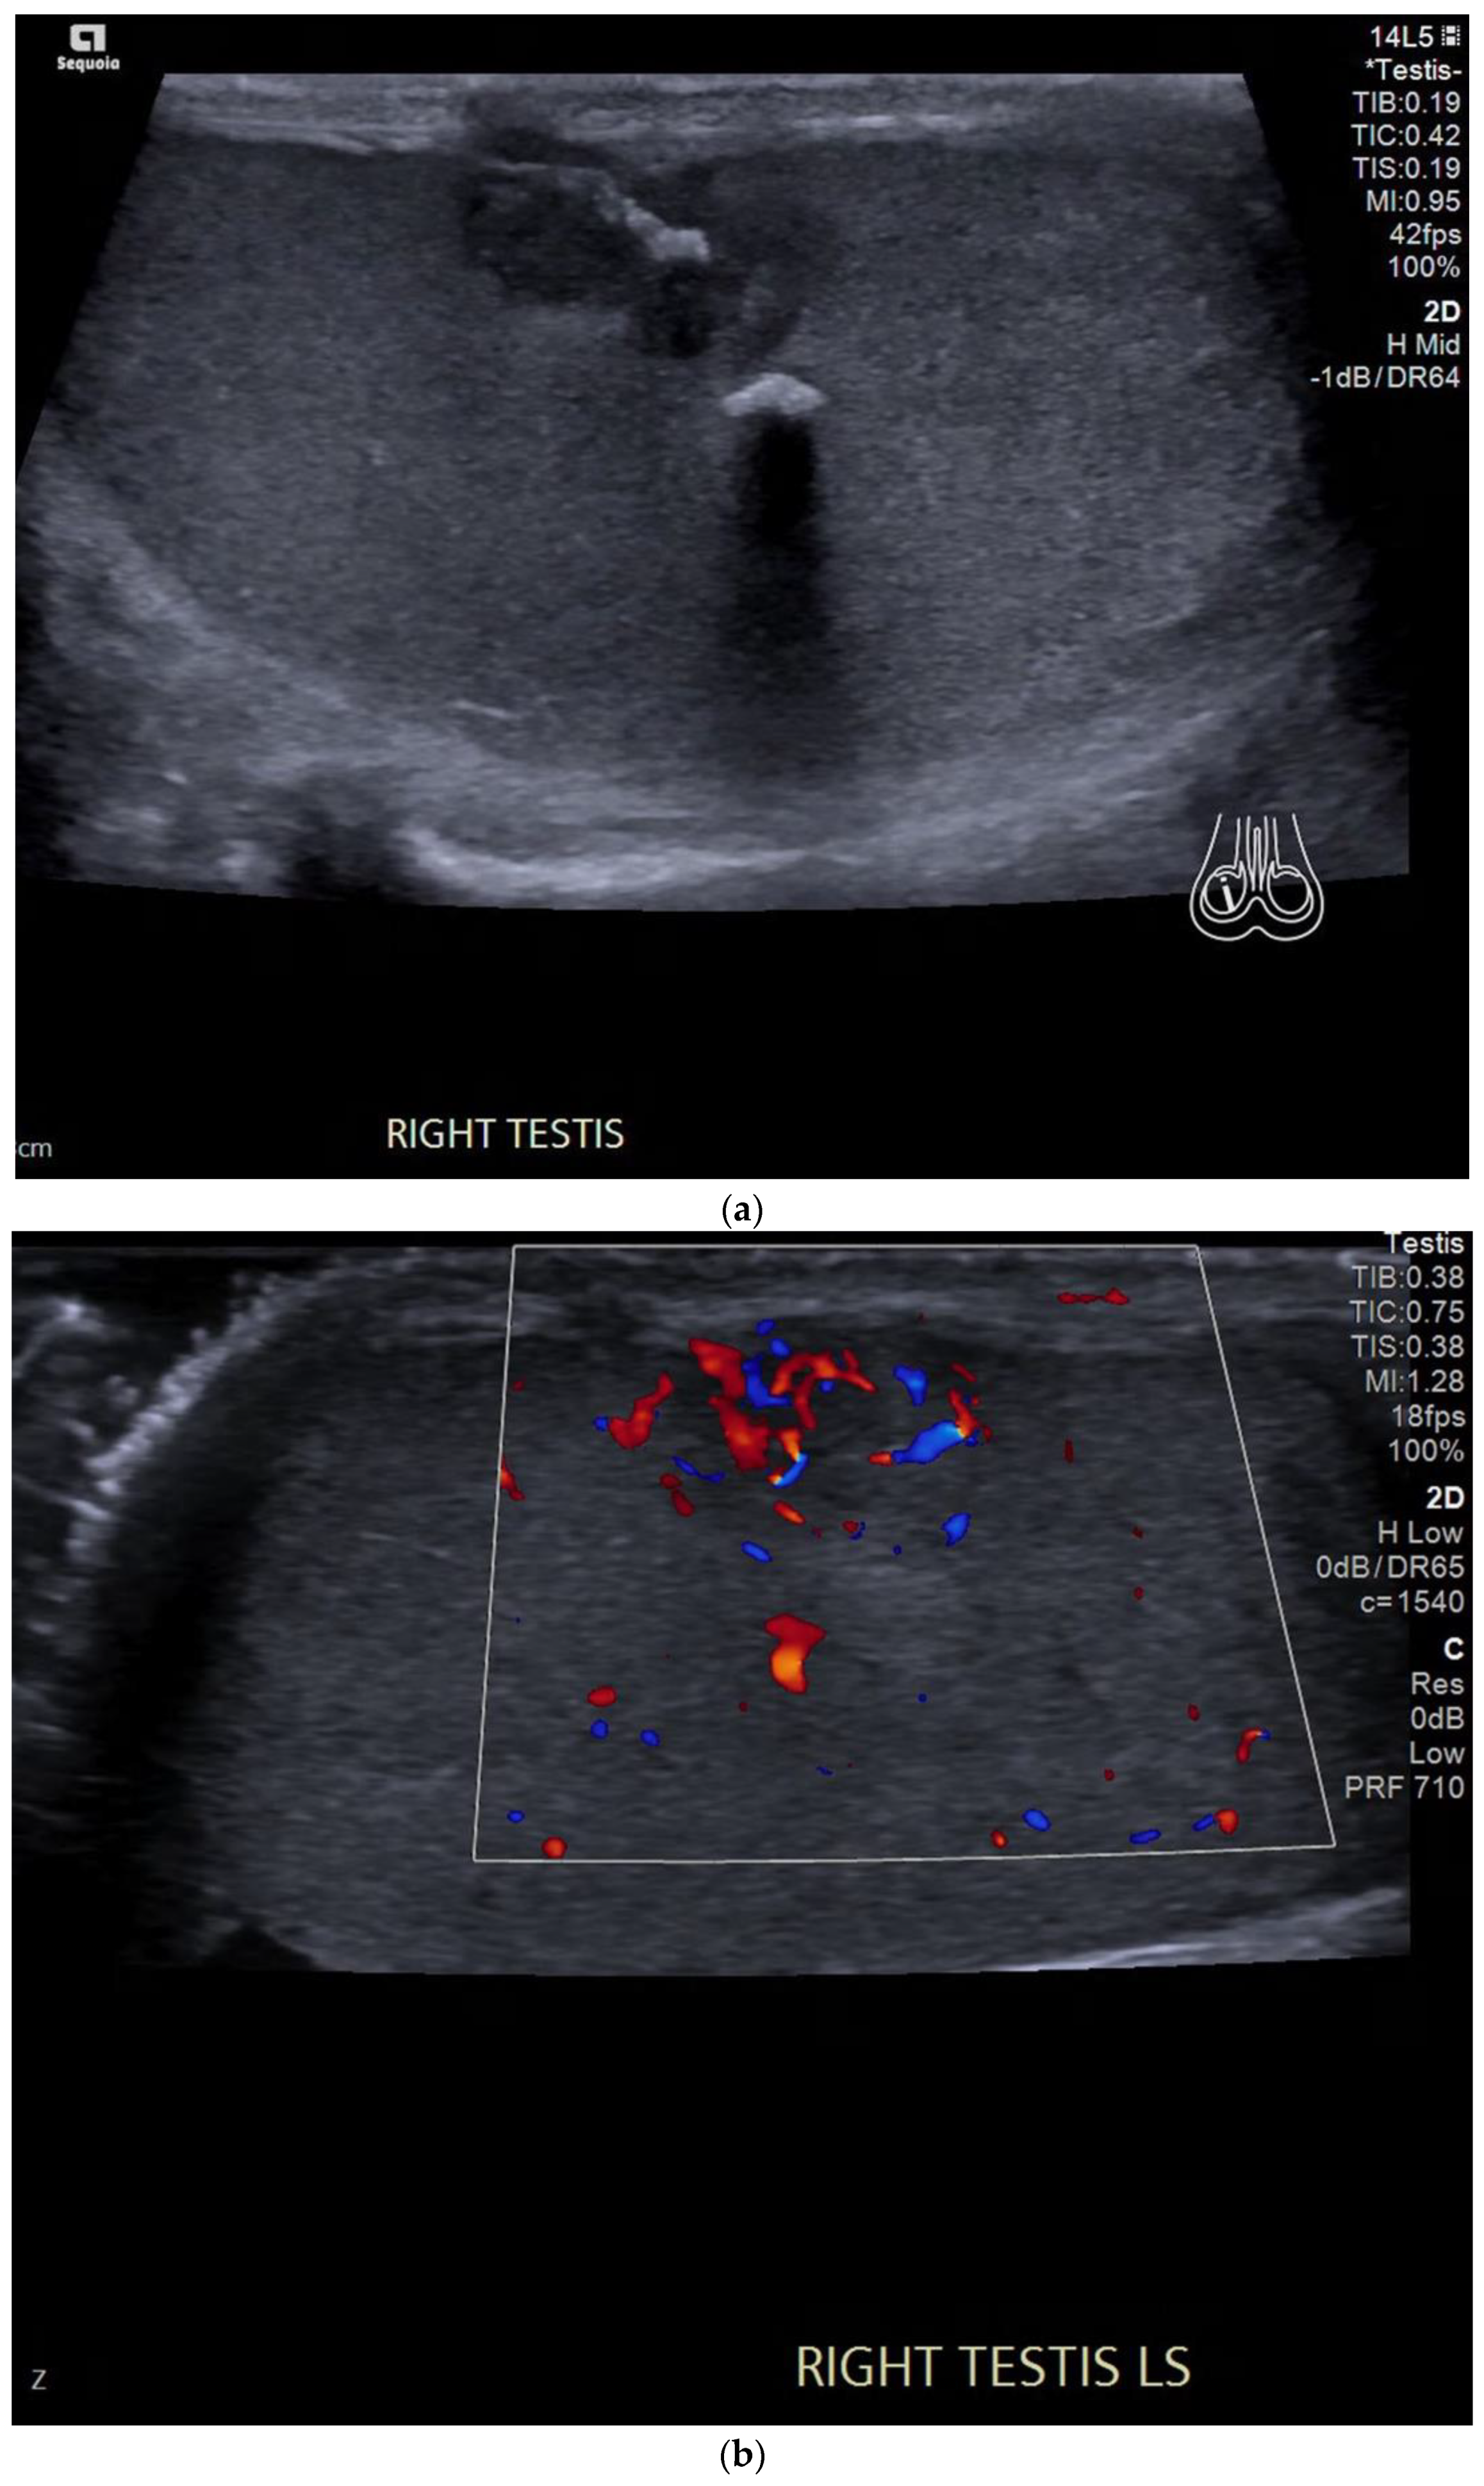

4.2. Non-Seminomatous Germ Cell Tumour (NSGCTs)

4.3. Embryonal Cell Carcinoma

| Pure embryonal | Heterogeneously hypoechoic Ill-defined margins with invasion of the tunica albuginea Can contain haemorrhage and calcifications |